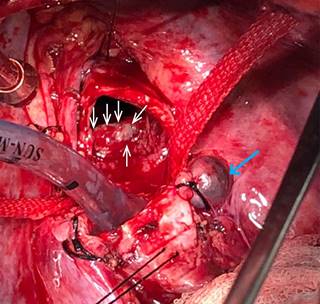

En nuestro centro se repitió la broncoscopia (Figura 2) encontrando tráquea de aspecto empedrada con poca visibilidad de anillos traqueales y un tumor acartonado, friable y sangrante, localizado en cara anterior de tráquea a 3.5 cm de la carina de aproximadamente 0.5 x 1.0 cm. Se realizó resección de 60% de la tumoración y hemostasia con adrenalina tópica. El resultado fue idéntico al de la primera biopsia. El paciente continuó con episodios de hemoptisis de 50-80 ml/día, por lo que se realizó una nueva broncoscopia cinco días después, observando tumoración de las mismas características (0.5 x 1.0 cm) sangrante. Se decide resección quirúrgica de segmento traqueal afectado.

Se realizó resección de tráquea por toracotomía posterolateral derecha. El paciente requirió intubación selectiva del bronquio principal izquierdo para colapsar pulmón derecho. El abordaje fue por el cuarto espacio intercostal donde se disecó y ligó la vena ácigos para proceder a la disección de tráquea, por medio de broncoscopio se delimitó el área de resección tumoral (Figura 3). La disección abarcó los 3-4 anillos contenedores del tumor (Figura 4), dejando márgenes de 1 cm superior e inferior. Se procedió a anastomosis terminoterminal realizada con vycril 3-0 (poligactina 910) puntos simples separados y reforzada con pleura vascularizada y cianoacrilato. Para verificar la ausencia de fuga se realizó maniobra de Valsalva a 40 cm de H20.

Una semana después se realiza broncoscopia de control que mostró una anastomosis íntegra y sin fugas. El resultado histopatológico de la pieza quirúrgica reveló un diagnóstico de hemangioma lobular capilar. El paciente fue dado de alta sin complicaciones, sin datos de estridor ni dificultad respiratoria. En la actualidad está en el tercer mes de seguimiento y clínicamente asintomático.